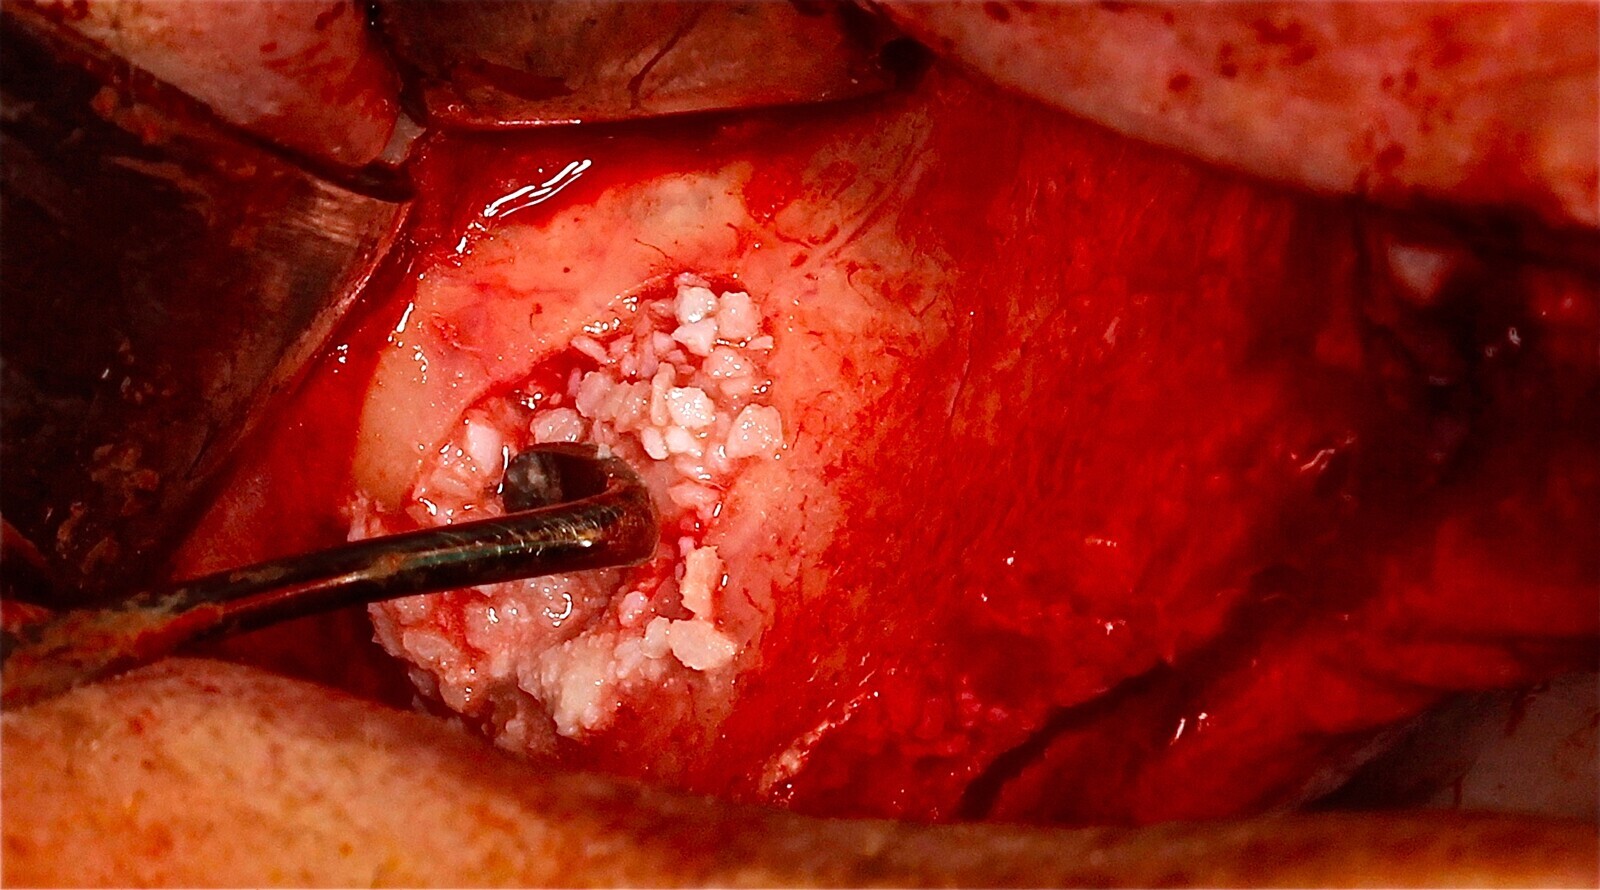

Fig. 15 Figura 15

5. Fijación del injerto previamente modelado al lecho con microtornillo de 1.5 a 2 mm de diámetro.

Fig. 16 Figura 16

6. Relleno de hueso particulado en la intersección entre el injerto óseo y el lecho receptor.